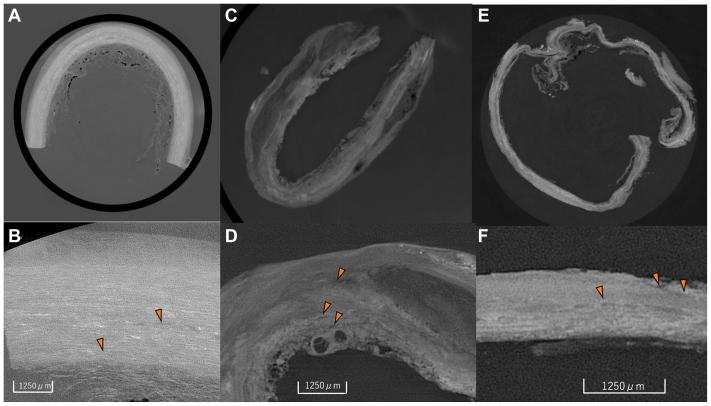

Human aortic specimens of the abdominal aorta were obtained during open repair, fixed with formalin, and analyzed among three groups. Group A was specimens from open abdominal aortic aneurysm repairs (n = 7). Group E was specimens from sac expansion without an evident endoleak after EVAR (n = 7). Group N was specimens from non-aneurysmal "normal" cadaveric abdominal aortas (n = 5). Using XPCT (effective voxel size, 12.5 μm; density resolution, 1 mg/cm), we measured the density of the tunica media (TM) in six regions of each sample. Then, any changes to the elastic lamina and the vasa vasorum were analyzed pathologically. The specimens were immunohistochemically examined with anti-CD31 and vascular endothelial growth factor antibodies.

The time from EVAR to open aortic repair was 64.2 ± 7.2 months. There were significant differences in the thickness of the TM among three groups: 0.98 ± 0.03 mm in Group N; 0.31 ± 0.01 mm in Group A; and 0.15 ± 0.03 mm in Group E ( < .005). There were significant differences in the TM density among the groups: 1.087 ± 0.004 g/cm in Group N; 1.070 ± 0.001 g/cm in Group A; and 1.062 ± 0.007 g/cm in Group E ( < .005). Differences in the thickness and density of the TM correlated with the thickness of the elastic lamina; in Group N, uniform high-density elastic fibers were observed in the TM. By contrast, a thinning of the elastic lamina in the TM was observed in Group A. A marked thinness and loss of elastic fibers was observed in Group E. CD31 immunostaining revealed that the vasa vasorum was localized in the adventitia and inside the outer third of the TM in Group N, and in the middle of the TM in Group A. In Group E, the vasa vasorum advanced up to the intima with vascular endothelial growth factor-positive cells in the intimal section.